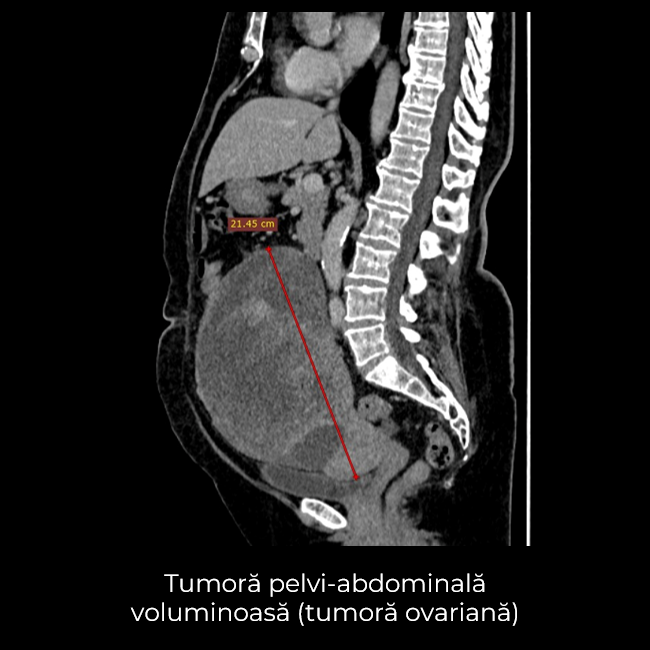

Uneori, o durere aparent banală ascunde în spate o realitate medicală mult mai serioasă. Așa s-a întâmplat și în cazul unei paciente de 63 de ani, care a ajuns la spital pentru dureri pelvine persistente. Investigația CT a schimbat însă complet perspectiva: au fost descoperite trei formațiuni tumorale în zone diferite ale corpului – o tumoră mamară stângă (carcinom mamar invaziv biopsiat), o tumoră pelvi-abdominală voluminoasă (tumoră ovariană) și o formațiune la nivelul peretelui posterior gastric (leiomiom gastric biopsiat).

- Histerectomie totală cu anexectomie bilaterală – îndepărtarea uterului și a ovarelor, cu verificarea histopatologică intraoperatorie a tumorii ovariene ce a relevat carcinom ovarian, limfadenectomie pelvină și interaortico-cava, omentectomie, biopsii peritoneale multiple.